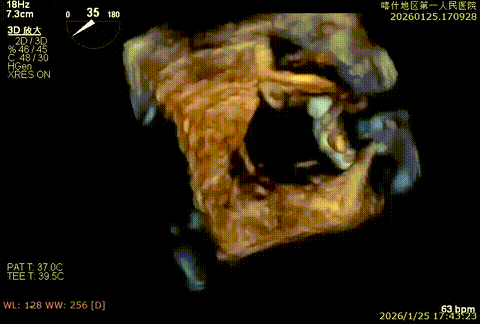

3D enface后叶栓系

3D enface观察反流

3D enface 观察脱垂

3D enface脱垂情况

X-plan 反流情况

该例患者为DMR类Barlows患者,二尖瓣重度反流,患者1,2,3区均可见脱垂,脱垂主要源于3区,反流主要源于3区。术前制定手术策略:使用一把XTR解决患者瓣叶脱垂与二尖瓣反流。术中进行房间隔穿刺后将XTR-CDS送入左心房,通过操控“M”旋钮,成功将二尖瓣夹定位于2区正上方。在2区进行弹道测试成功后,进行Orientation调整。在3区将二尖瓣夹送入左心室,成功捕捞和夹持瓣叶后缓慢关紧夹臂,解决大部分反流,Saide by Saide L植入第二把XTR。TEE检查见二尖瓣反流程度充分降低至1+,二尖瓣双孔组织桥稳定,跨瓣压差3mmHg,肺静脉逆流改善明显,手术安全结束。